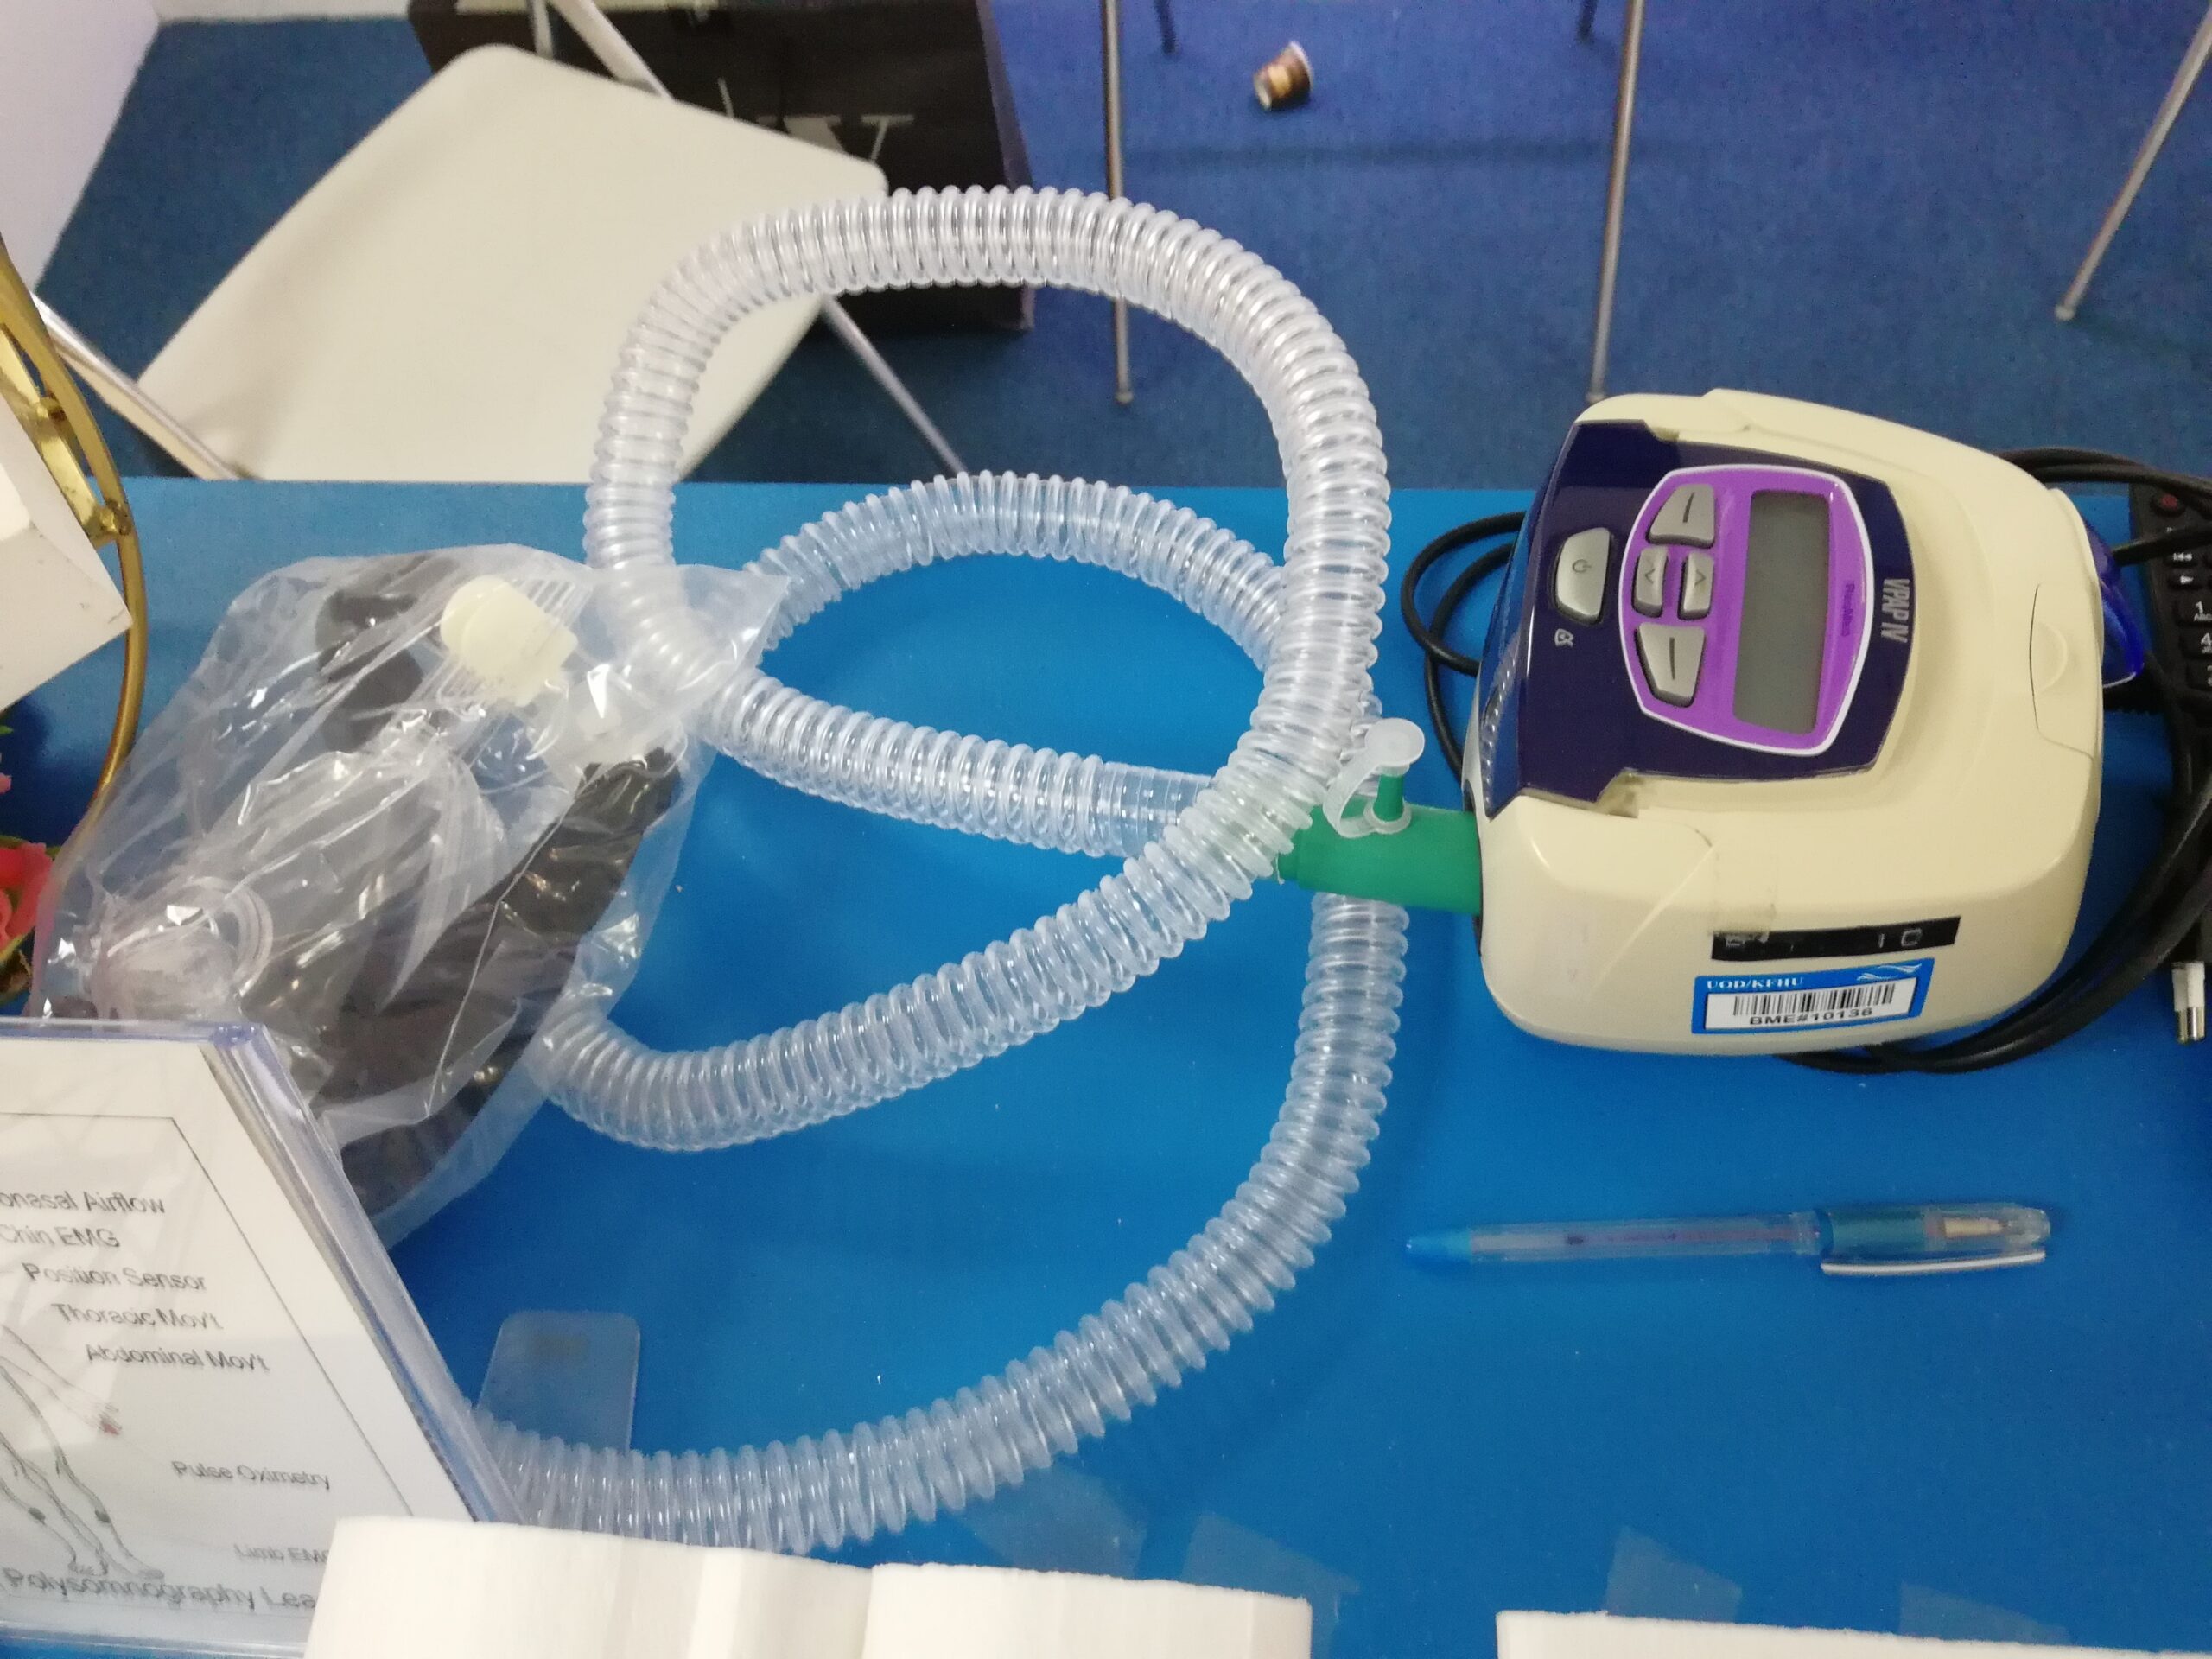

- High flow nasal cannulae – consists of wider – bore prongs and offers humidification and titration of oxygen concentrations to be delivered.

- Continuous positive airway pressure (CPAP) – machine supplied continuous positive pressure during the entire breathing cycle causing better oxygenation by narrowing the shunt (i.e., inadequate alveolar ventilation). This is generally using in high dependency units.